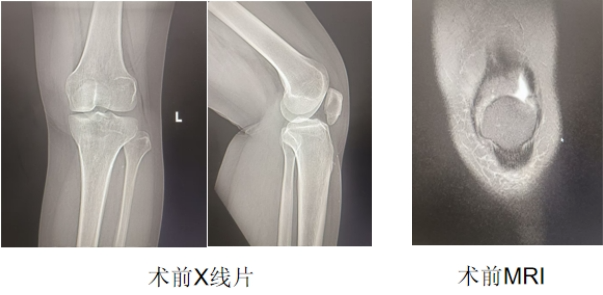

运动医学科庞军主任医师接诊患者后,发现其左膝低位髌骨,左大腿肌肉明显萎缩,伸膝无力,行走时易摔跤,下蹲困难,髌骨上缘股四头肌外侧按压空虚,下缘压痛明显。完善相关影像检查并结合患者病史,考虑患者左膝股四头肌陈旧性损伤,因未规范治疗及康复,已发展为左膝髌腱挛缩、低位髌骨,建议患者住院接受治疗。

在与患者及家属沟通并征得同意后,由运动医学科北京专家孟庆阳主刀,殷向辉、范冰洋医师协助,为患者实施了开放性左膝陈旧性股四头肌损伤修补成形+髌韧带松解成形手术。术后当天,患者患膝即可抬离床面;术后第二天,患者便能佩戴支具下地活动,后续康复师指导训练恢复良好,现已顺利出院。